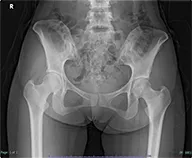

Vol.08[左臀部痛]

自宅でダンスの練習中に左殿部に違和感が出現し、徐々に増悪してきた。近医整形外科や内科を受診するも特に異常を指摘されず、時々38度台の発熱があり、感染症を疑われて抗生剤を処方されたことがあるが、症状改善なかったため、精査加療目的に当科紹介となった。